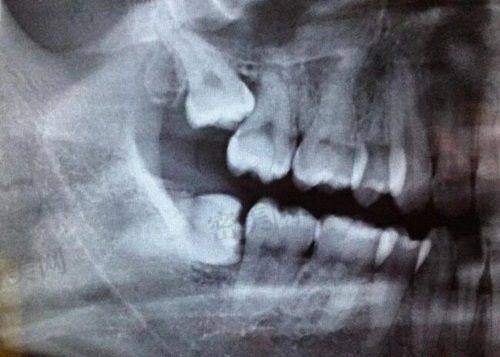

在设备上,门诊部从正规渠道获得器械和材料。良好的设备是开展各类口腔项目的基础,能为医生的操作提供有力的支持,也有助于提高治疗的成效和正确性。

在牙齿矫正项目上,慈溪牙牙乐口腔门诊部的医生对方案把控到位。牙齿矫正需要根据患者的具体情况制定个性化的方案,医生能够正确地把握方案,意味着可以为患者提供更合适的矫正方式,从而达到较好的矫正成效。

在种植牙领域,医生也有一定的技术优势,包括单颗牙和多颗牙种植。门诊部提供预约服务,方便患者合理安排时间。患者在进行种植牙手术时,无论是单颗牙缺失还是多颗牙缺失,都能在这里得到相应的治疗。